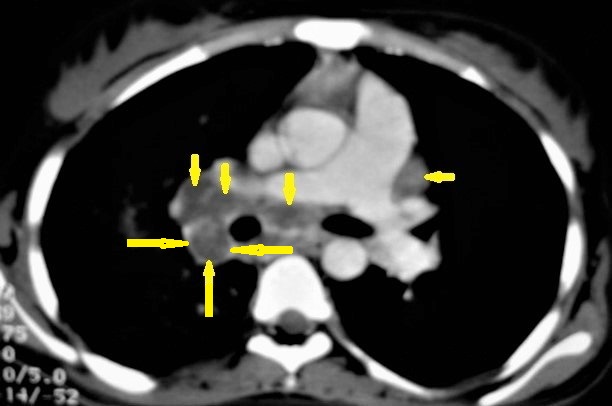

Figure 1. Primary TB in an 18-year-old man. Axial mediastinal-window CT image shows multiple enlarged mediastinal lymph nodes (short arrows), and right hilar lymph nodes are characterized by central low density and peripheral enhancement after contrast administration forming the rim sign (long arrows).